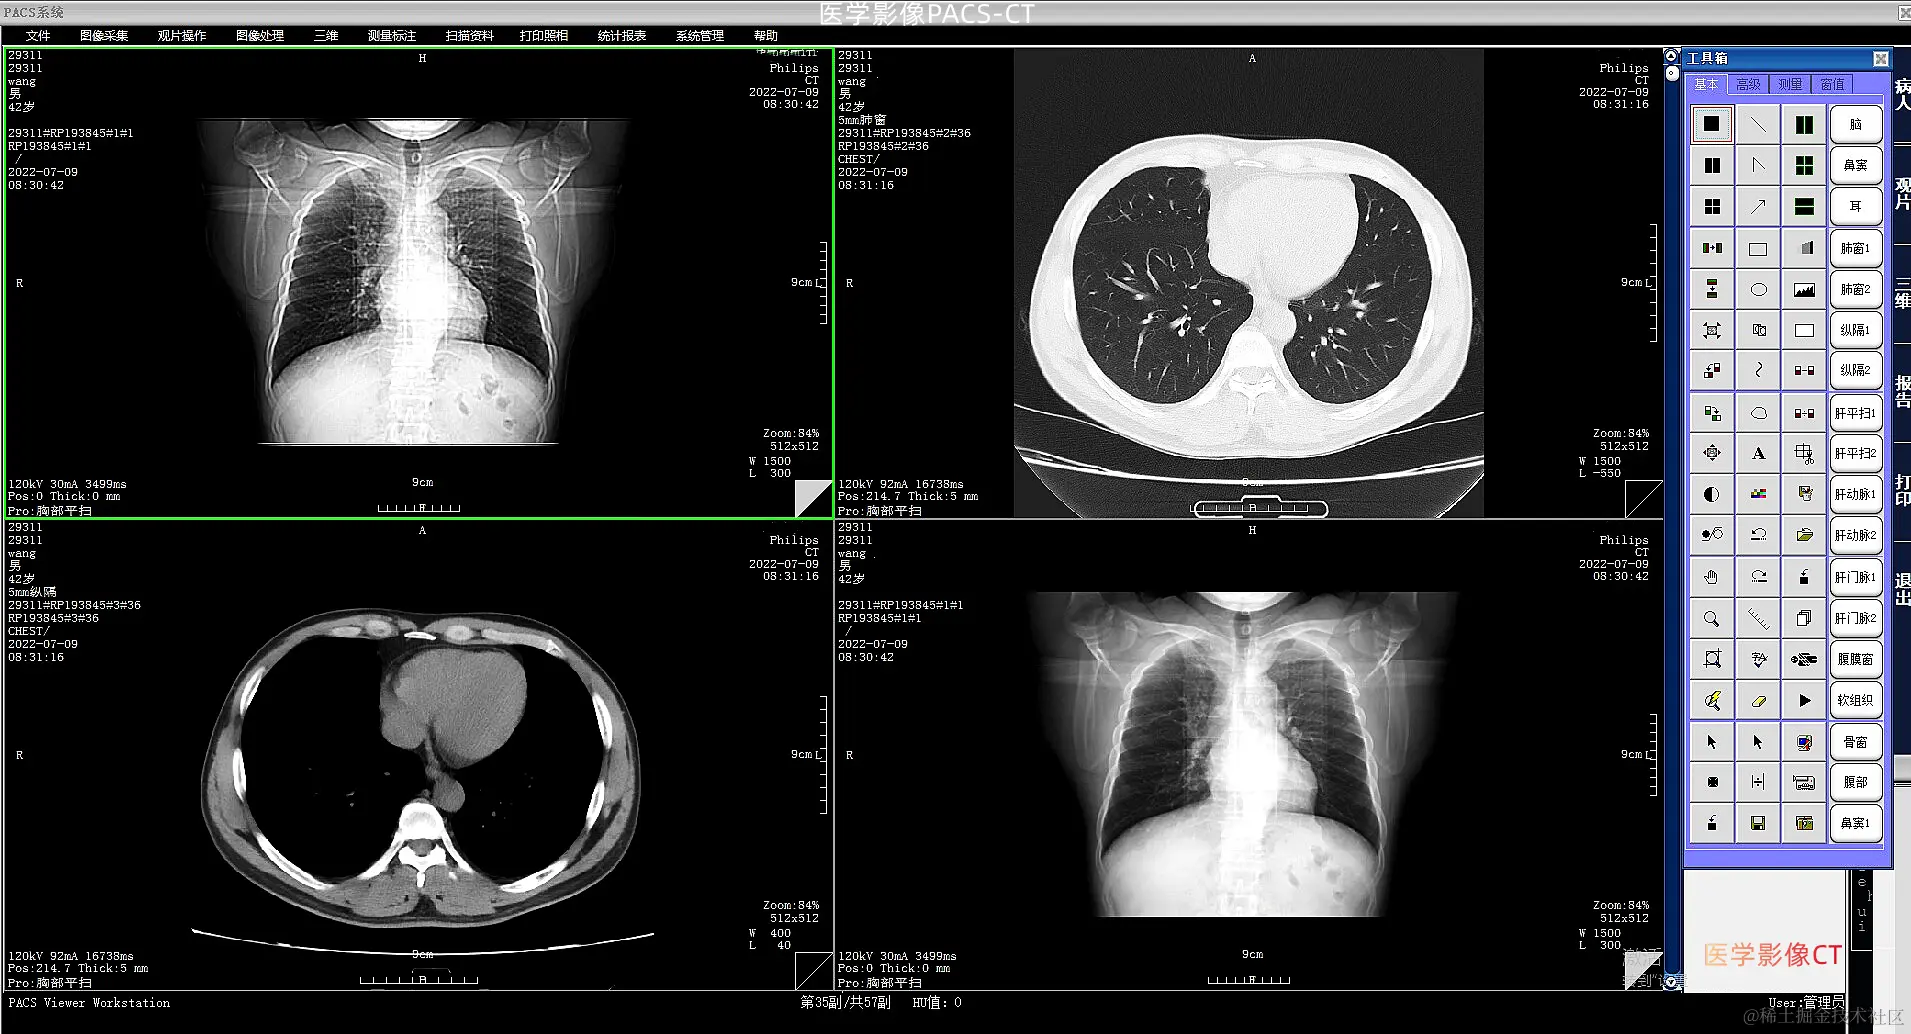

狭义的医学影像信息系统是指基于医学影像存储和通信系统的管理系统,从技术上解决了影像处理技术。临床信息系统是指支持医院医务人员临床活动,收集和处理患者临床医疗信息的信息管理系统。放射科信息系统是指放射科挂号、分诊、影像诊断报告、信息查询、统计等基于流程管理的信息系统。医院信息系统是指覆盖医院全部业务和全过程的信息管理系统;实验室信息系统是一种用于处理实验室过程信息的信息系统。

在现代医疗行业中,医学影像信息系统包括RIS,按照DICOM3.0国际标准设计,是由高性能服务器、网络和存储设备组成的硬件支撑平台,以大型关系数据库作为数据和影像的存储和管理工具,以医学影像的采集、传输、存储和诊断为核心。它是集图像采集、传输和存储管理,图像诊断查询和报告管理、综合信息管理等功能于一体的综合应用系统。其主要任务是保存各种医学图像(包括核磁共振、CT、DR、超声、各种X光机等产生的图像。)由医院影像科通过DICOM3.0国际标准接口(中国市场多为模拟、DICOM、网络等接口)以数字化方式生成。

PACS系统的概念已从原来将数字化的医学影像通过网络传送到连接在网络上的影像显示工作站上作一般显示和进行数字化存储,发展成为以数字化诊断(无纸化、无胶片化)为核心的整个影像管理过程,包括:数字影像采集、数字化诊断工作站、影像会诊中心,网络影像打印管理、网络影像存储、网络影像分发系统和网络影像易示计算机,网络综合布线和数据交换系统等

PACS系统将医学影像设备资源和人力资源进行更合理和有效的配置,通过计算机对影像进行数字化获取、处理、存储、调阅、检索,使影像科室医生可以为病人提供更快和更好的服务;临床医生通过网络快速调阅病人图像及诊断报告,实现图像资源共享。

以数字化诊断为核心的PACS系统可以节约胶片使用量,节省胶片存储成本,对影像科室进行科学的管理,提高影像诊断水平和影像科室工作效率。而这种真正意义上的PACS系统必须要解决所有影像接口问题、系统的工作流程问题、与医院信息系统的副合问题以及可视化问题、压缩技术问题等.